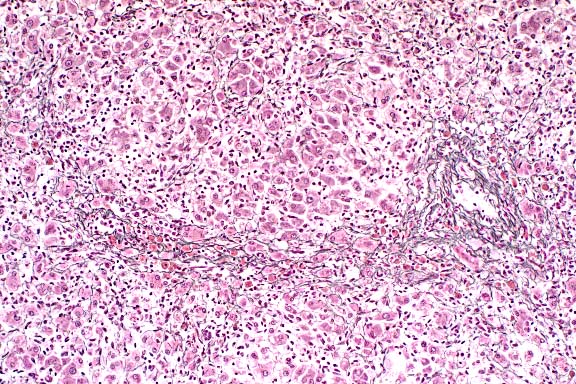

- In sections of both lobes of the thyroid gland, follicles

are small and lack colloid. Follicular epithelial cells are columnar

to polygonal and occasionally bilayered. The cytoplasm is eosinophilic,

abundant, and contains large, clear, poorly defined vacuoles.

Basal to central nuclei are large (up to 15 mm in diameter),

round and have coarsely stippled chromatin.

10x

obj

- Case14-1. Thyroid. There is diffuse follicular epithelial

hypertrophy and hyperplasia. Relatively few follicles have discernable

lumens or colloid production.

40x

- Case14-1. Thyroid. Follicular epithelium is hypertrophic

and vacuolated. Follicle colloid is globular and sparce.